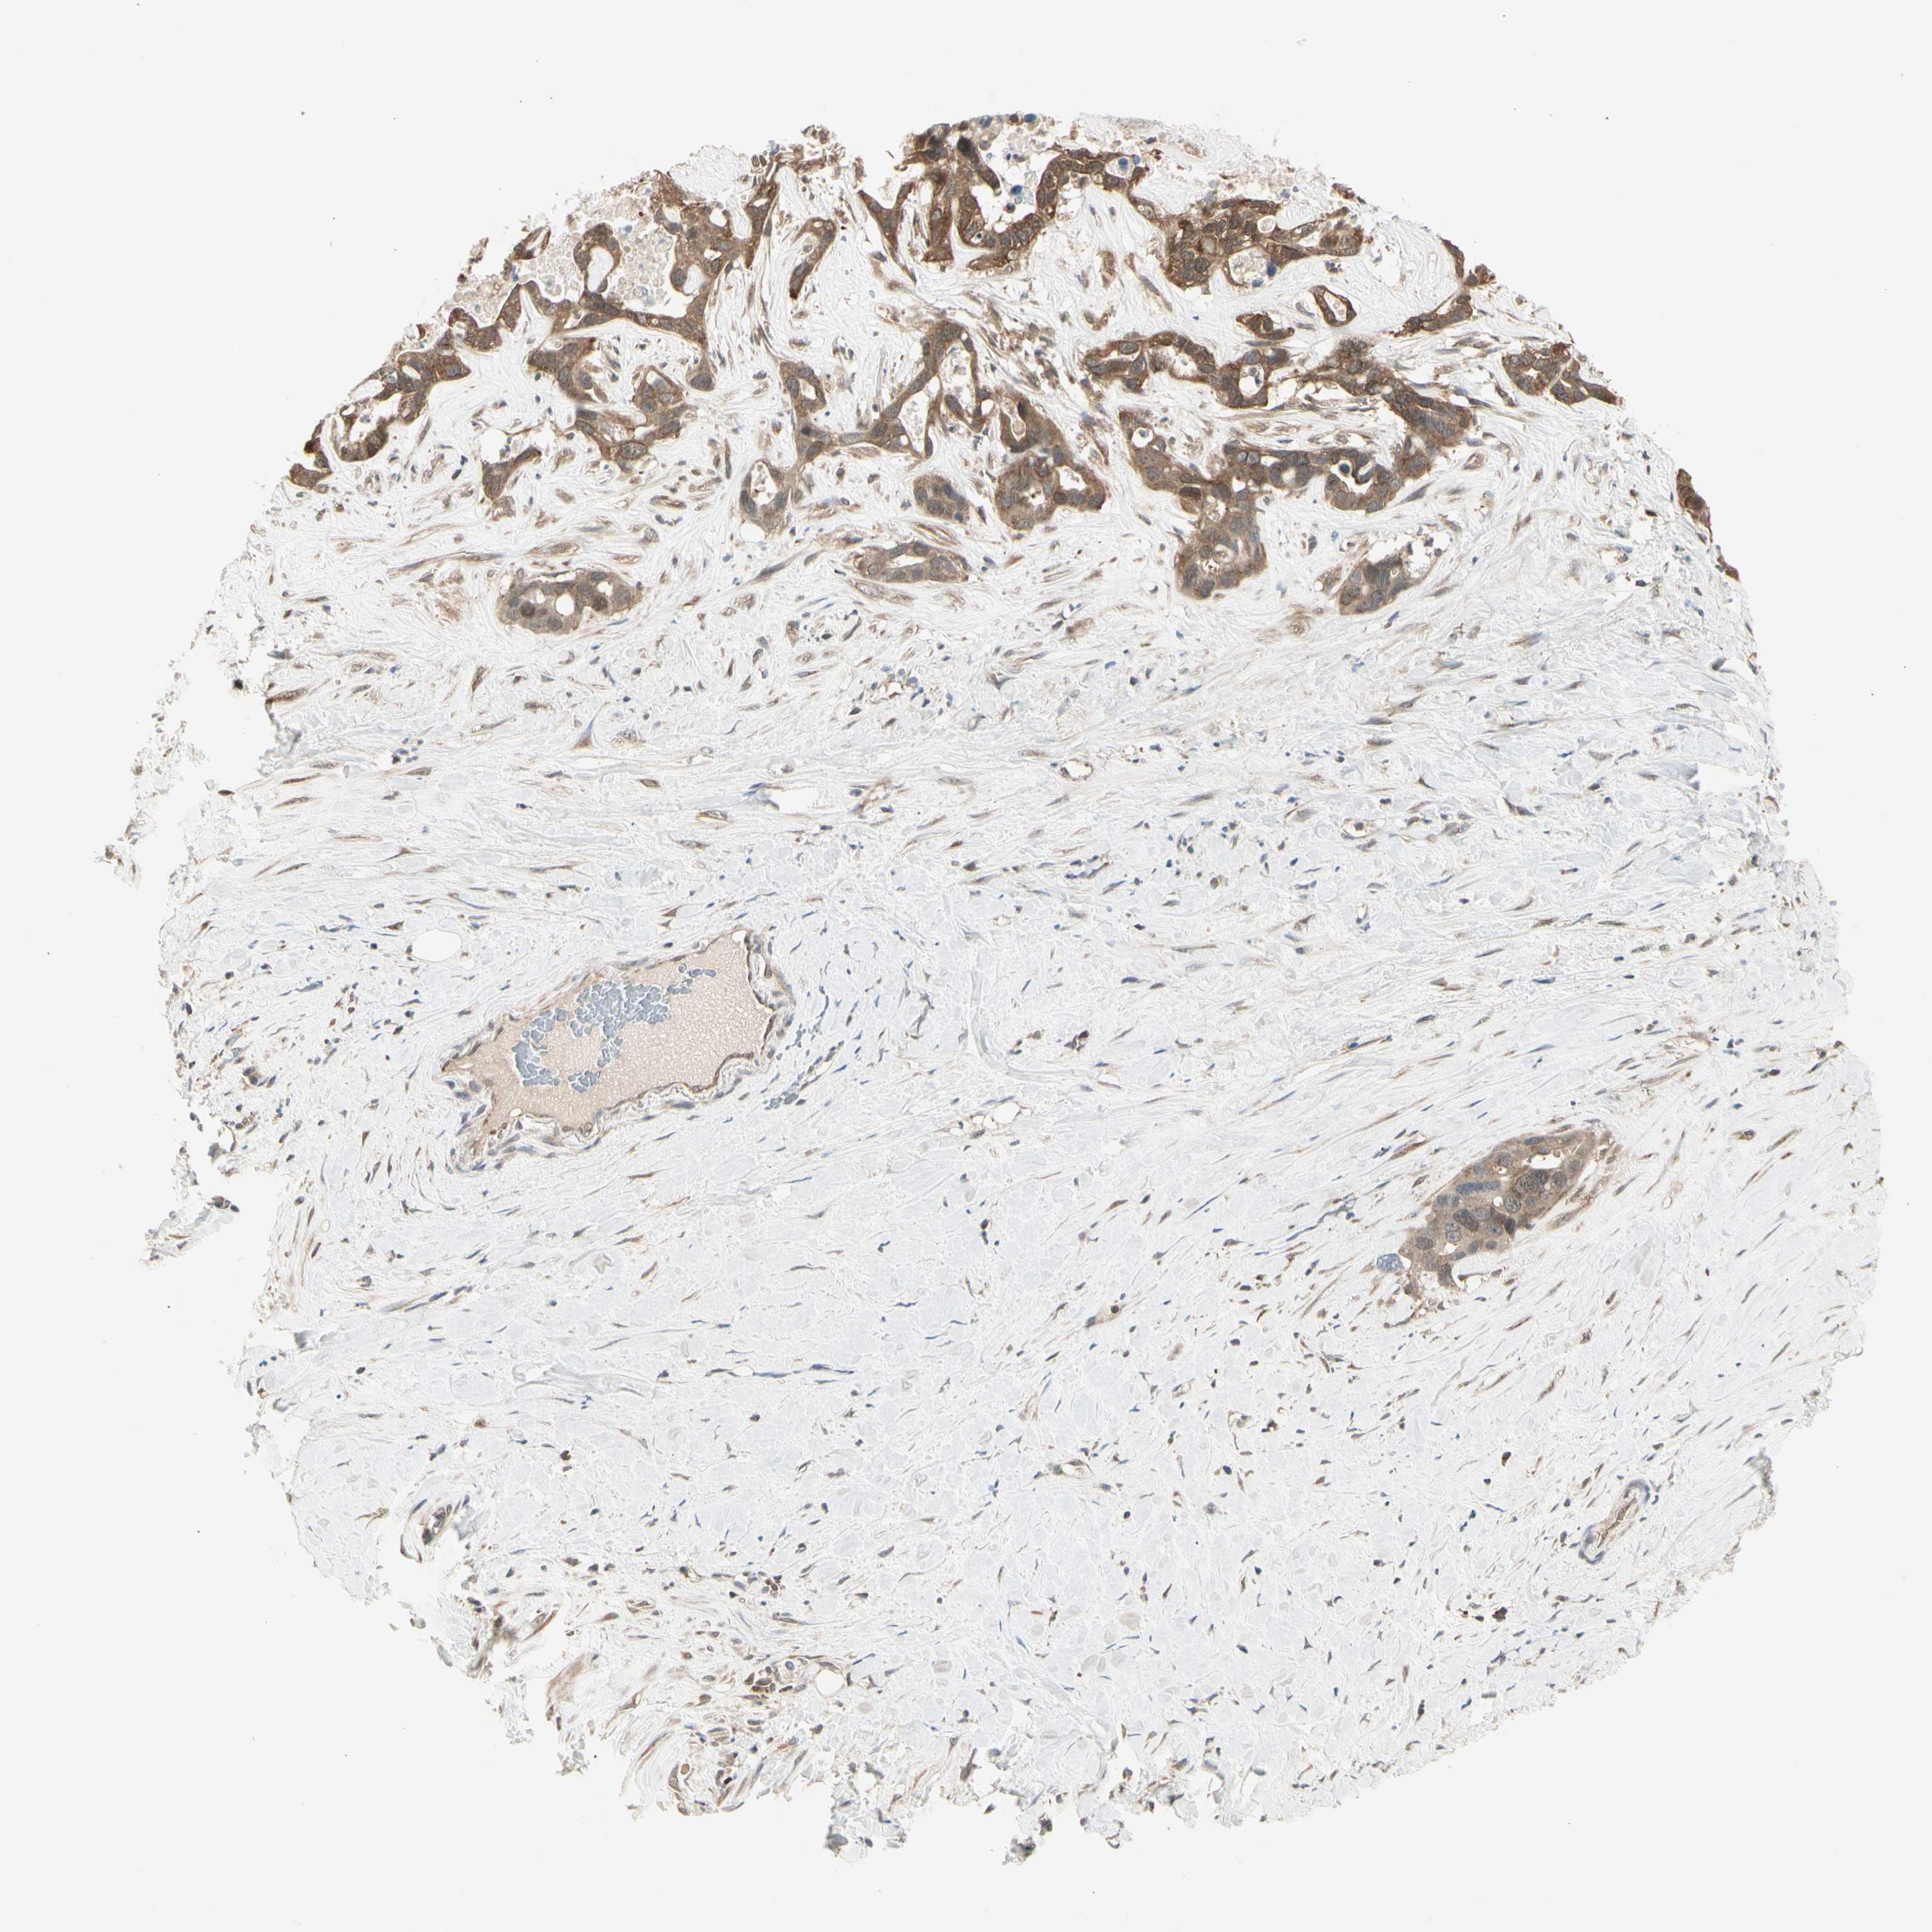

LIVER CANCER - Protein expressioni

A mouse-over function shows sample information and annotation data. Click on an image to view it in a full screen mode. Samples can be filtered based on level of antibody staining by selecting one or several of the following categories: high, medium, low and not detected. The assay and annotation is described here.

Note that samples used for immunohistochemistry by the Human Protein Atlas do not correspond to samples in the TCGA dataset.

Antibody stainingi

Antibody staining in the annotated cell types in the current human tissue is reported as not detected, low, medium, or high, based on conventional immunohistochemistry profiling in selected tissues. This score is based on the combination of the staining intensity and fraction of stained cells.

Each image is clickable and will lead to virtual microscopy that enables deeper exploration of all samples and also displays staining intensity scores, fraction scores and subcellular localization as well as patient and tissue information for each sample.

Antibody HPA008237

Antibody CAB017181

Staining

High

Medium

Low

Not detected

Intensity

Strong

Moderate

Weak

Negative

Quantity

>75%

75%-25%

<25%

None

Location

Nuclear

Cytoplasmic/membranous

Cytoplasmic/membranous,nuclear

Cholangiocarcinoma

Carcinoma, Hepatocellular, NOS